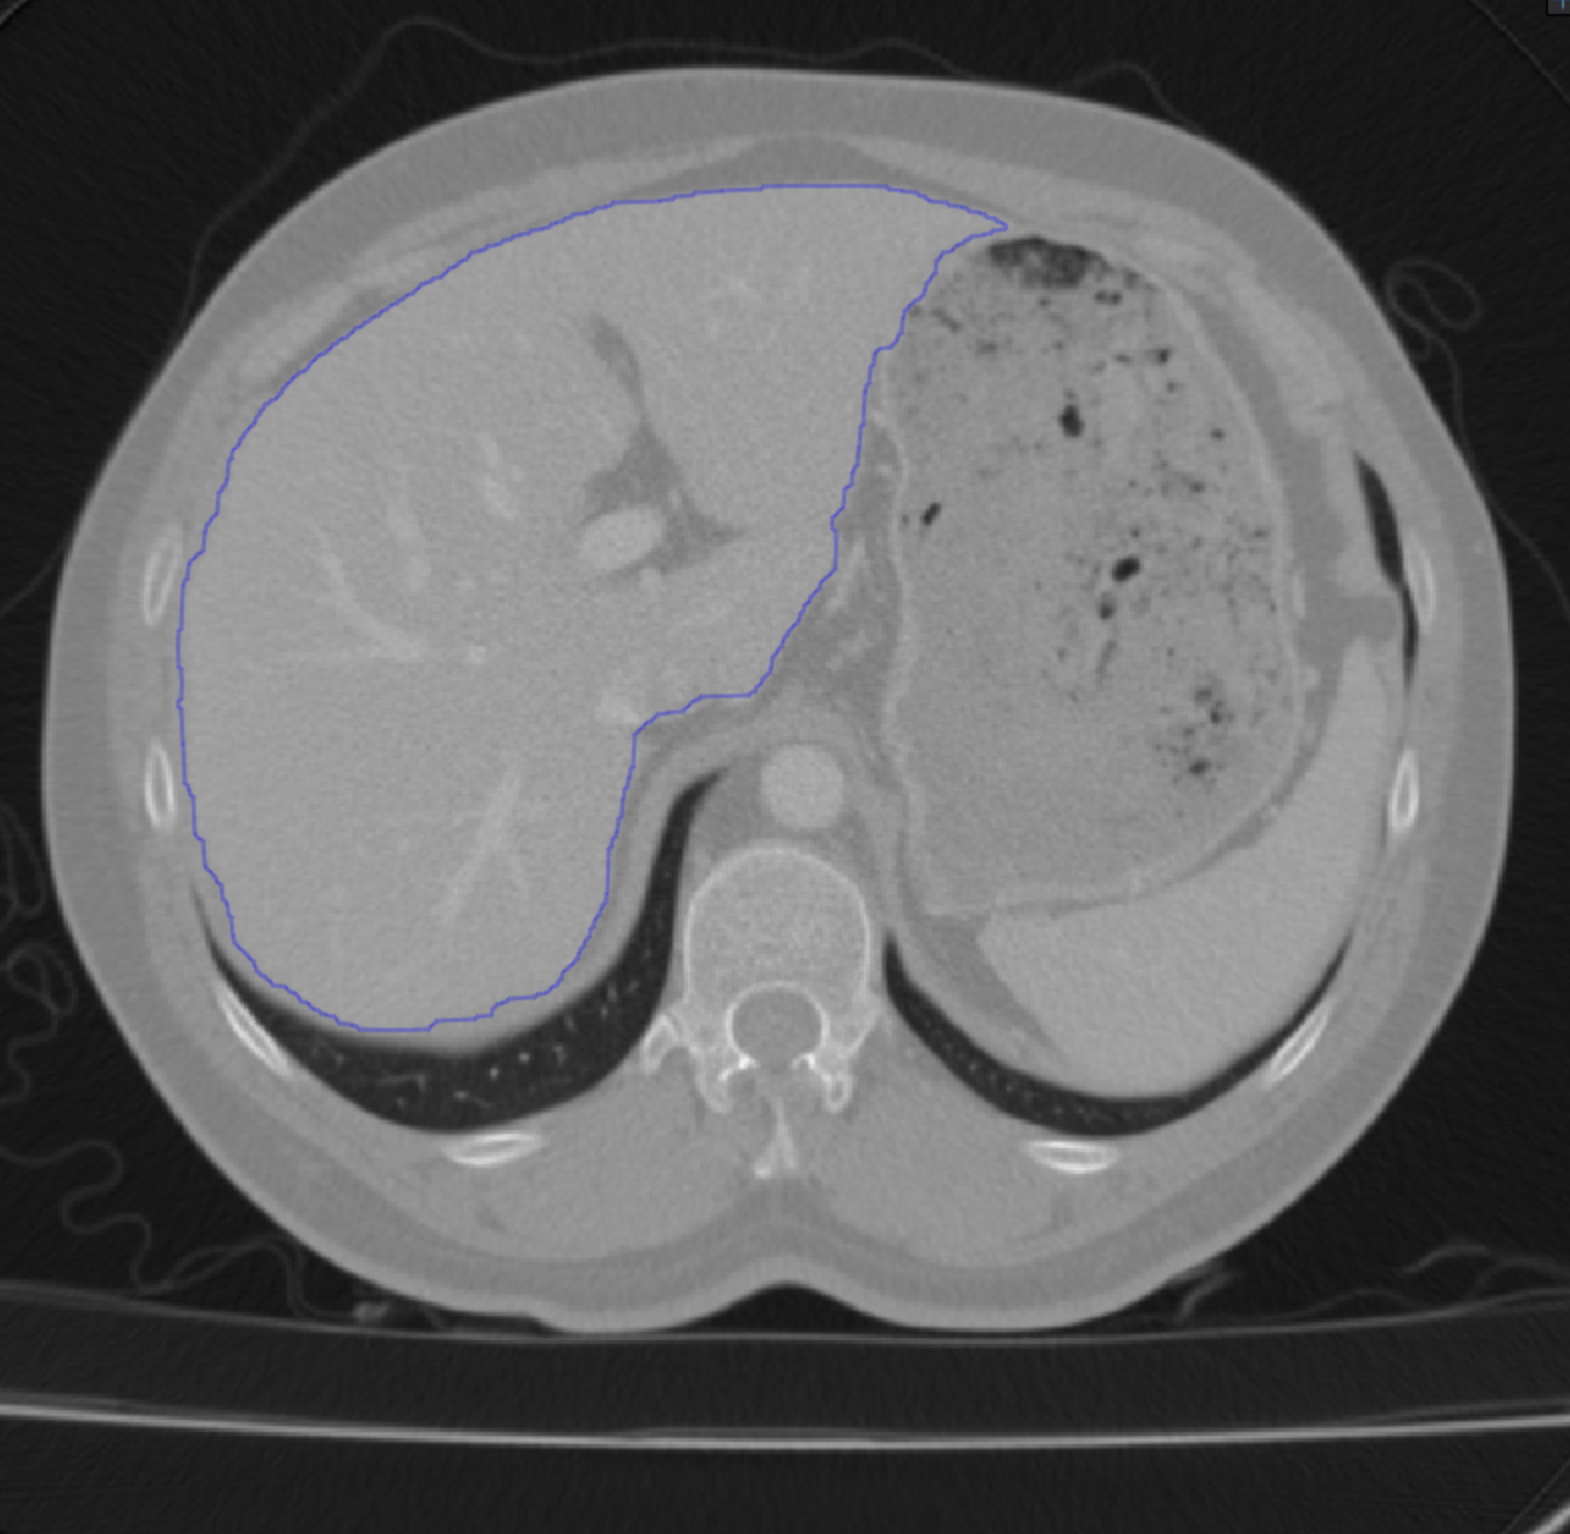

Our approach to training a network involves an annotator providing only a sparse set of 3D points on the surface of target objects for each image volume, as opposed to carefully annotating several individual slices in each. These points are used to deform a template, such as those shown in Fig. 1, using active surface models [26]. This provides a rough indication of where the target object boundary is. Weak-Net uses it to learn weights that yield accurate object boundaries. In short, we provide minimal human input at training time so that, at inference time, the trained network can be used without human intervention.

The template of Eq. 1 should approximately match the target structure. Hence, the annotator should supply points that are distributed across the object surface. These points are then used to deform the template. In practice, For structures of genus 0, we start from a simple spherical template but more complex ones are possible. As we increase the number of points, we get increasingly refined templates, as shown in Fig. 4.

To perform this deformation interactively, we developed a GUI that relies on Active Surface Models (ASMs) [26] implemented as a MITK [28] plugin. It lets the annotator supply a few points by clicking on 2D cross sections of the input image volume. The ASM then deforms the template in real-time and overlays it on the image data, both as 2D cross sections and 3D surface renderings. The annotator can then add more points wherever the deformed template is too far from the target organ’s boundary and iterate as often as necessary. This effectively puts the human in the loop in a painless and practical way. We illustrate this in a video that can be found in the supp. material.